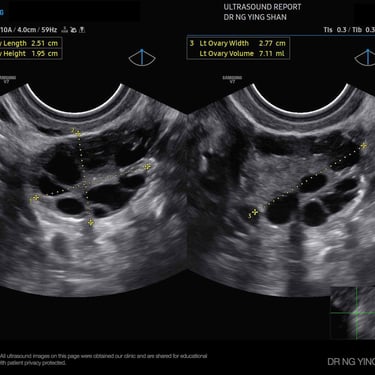

The ovaries and developing eggs (follicles)

Ovarian cysts (fluid-filled sacs in the ovary)

PCOS (polycystic ovary syndrome)

Polycystic Ovary